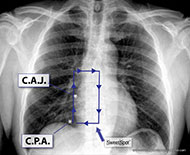

The SWEET SPOT™ is a rectangular template superimposed on a frontal CXR, whose margins and internal area are acceptable for VAD catheter tip position. This is tailored to the individual patient's chest x-ray. As such, it has no fixed length or width but does have fixed proportions with the craniocaudal length being twice the width on a frontal chest x-ray. Depending on patient anatomy, it can exceed 8 x 4 cm. The template (see Figure 01) is simply compared in size to the CXR at hand. This template is very easy to memorize and just as easy to teach.

The SWEET SPOT™ also has a fixed center point. It is centered over what I believe is the most accurate radiographic estimation of the cavo-atrial junction, i.e. on a frontal CXR, the initial outward bulge of the lower right cardiomediastinal margin due to the transition from the smaller, more tubular superior vena cava to the more capacious and rotund right atrium. It was designed to be twice as wide as the lower third of the SVC to allow for the curving course of many catheter tips as they enter the right atrium - especially with left-sided access. The SWEET SPOT™ extends from the lower third of the SVC to the most inferior extent of the right atrium - stopping at the frontal CXR's cardiophrenic angle (see Figure 01).